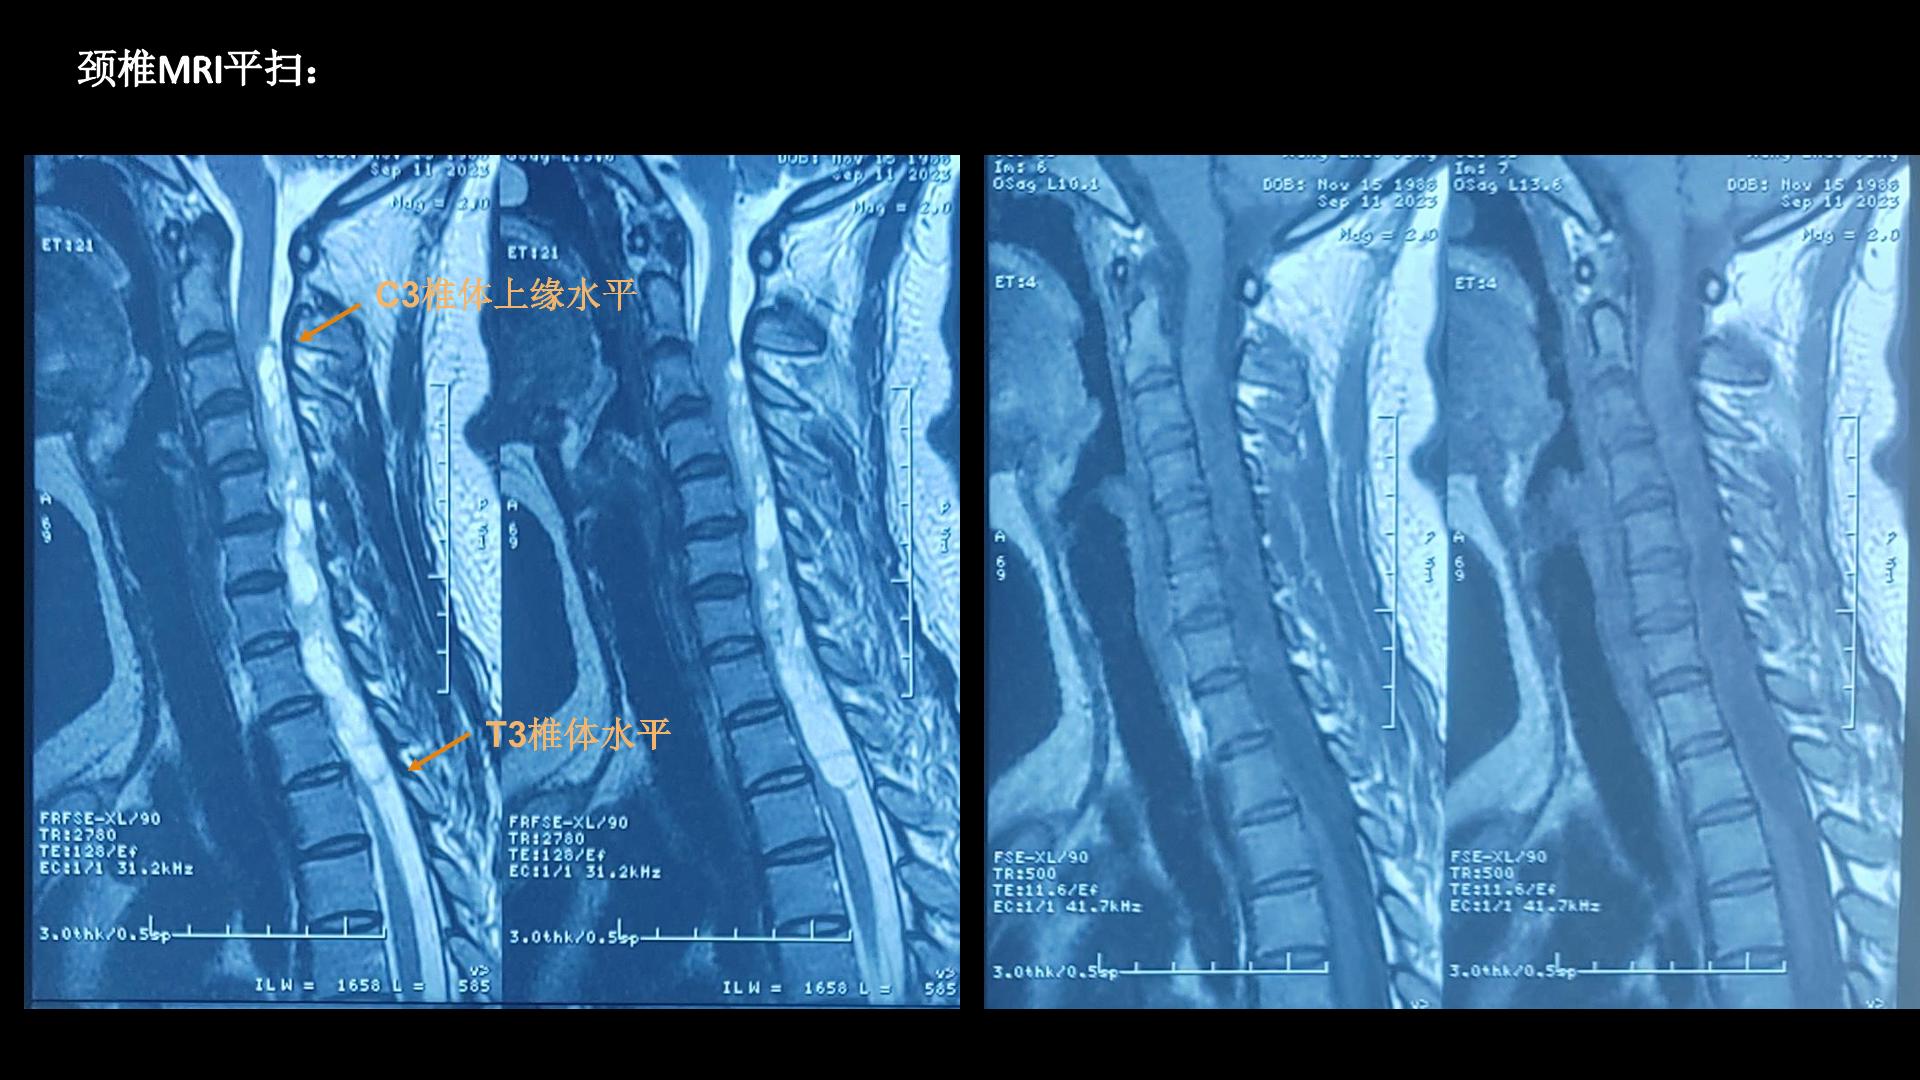

西安交通大学第二附属医院刘重霄教授团队:一例巨长型颈胸椎神经鞘瘤切除术+脊柱内固定术